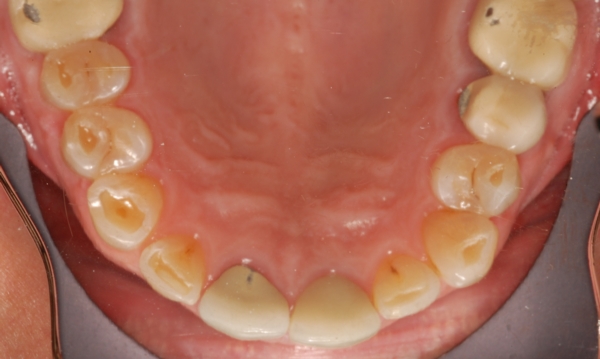

Начальная стадия кариеса с зубным налетом, которая поддается лечению в домашних условиях.